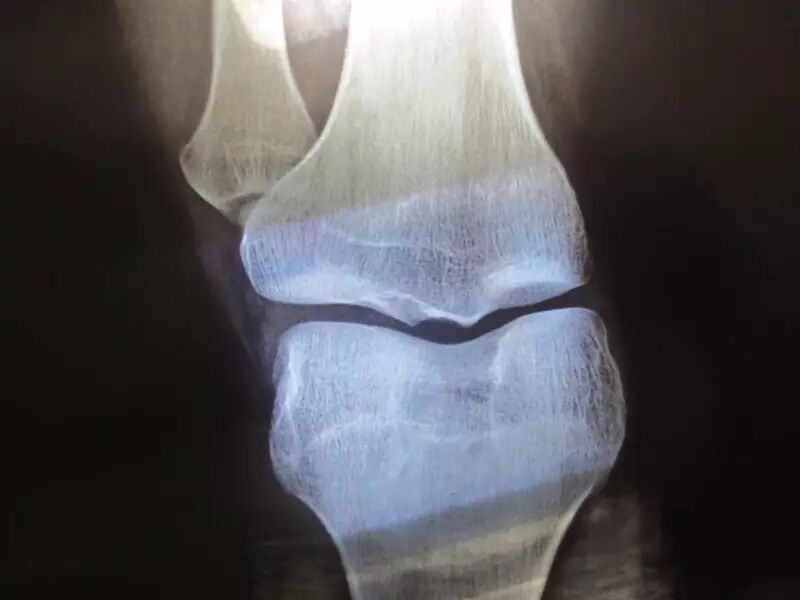

“从骨龄片上看,孩子骨骺已经闭合了,如果早点儿来看,还有办法,现在太晚了。”门诊副主任桂林艳遗憾地说。

图据网络

一般来说,女孩子的骨龄如果超过15岁,男孩的骨龄如果超过17岁,这时的骨骺大多已经闭合,长高的机会就非常小了。

因此,越早了解骨骺闭合情况,越早干预,越能够对孩子进行更好的干预治疗。